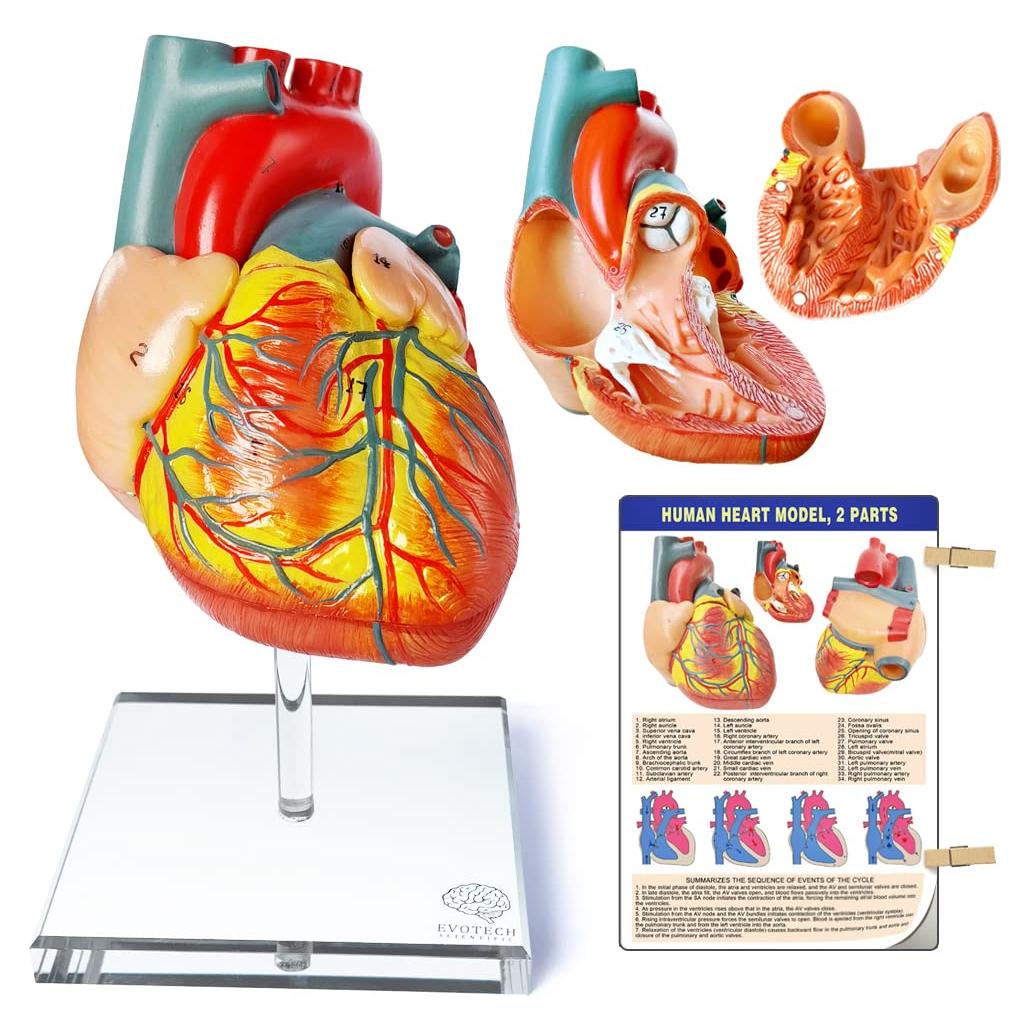

Modelos Anatómicos 3D EVOTECH SCIENTIFIC - Cuerpo, Corazón y Esqueleto